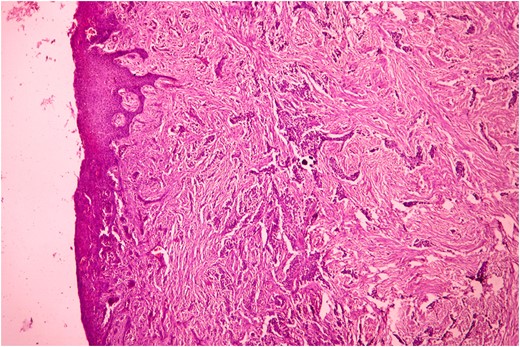

Her younger sister with age 17 years also presented 4 months later with similar complaints (Fig. 4). She also had normal deciduous teeth but did not have any permanent teeth eruption. She had difficulty in mastication and speech as well. She was mentally sound and did not have any other abnormalities. All her routine investigations were normal. X-ray (Fig. 5) and CT (Fig. 6) scan showed permanent teeth in both upper and lower arch which were malpositioned, unerupted and impacted in fibrous growth. Biopsy was taken from the gingival growth of younger sister which showed stratified squamous lining and subepithelial tissue showed collagenous fibrous connective tissue with mild chronic inflammatory cells (Fig. 7). Diagnosis of FGF was given. She underwent two stage gingivectomy 2 weeks after the initial diagnosis of FGF (Fig. 8). She is doing well and able to close her lips on post-operative follow-up (Fig. 9A). Later, prosthetic rehabilitation was done with upper and lower complete removable denture to the younger sister (Fig. 9B).

Histopathological picture of younger sister showing stratified squamous lining and subepithelium shows rich collagenous fibrous connective tissue with mild inflammatory cells. (H&E, ×400).